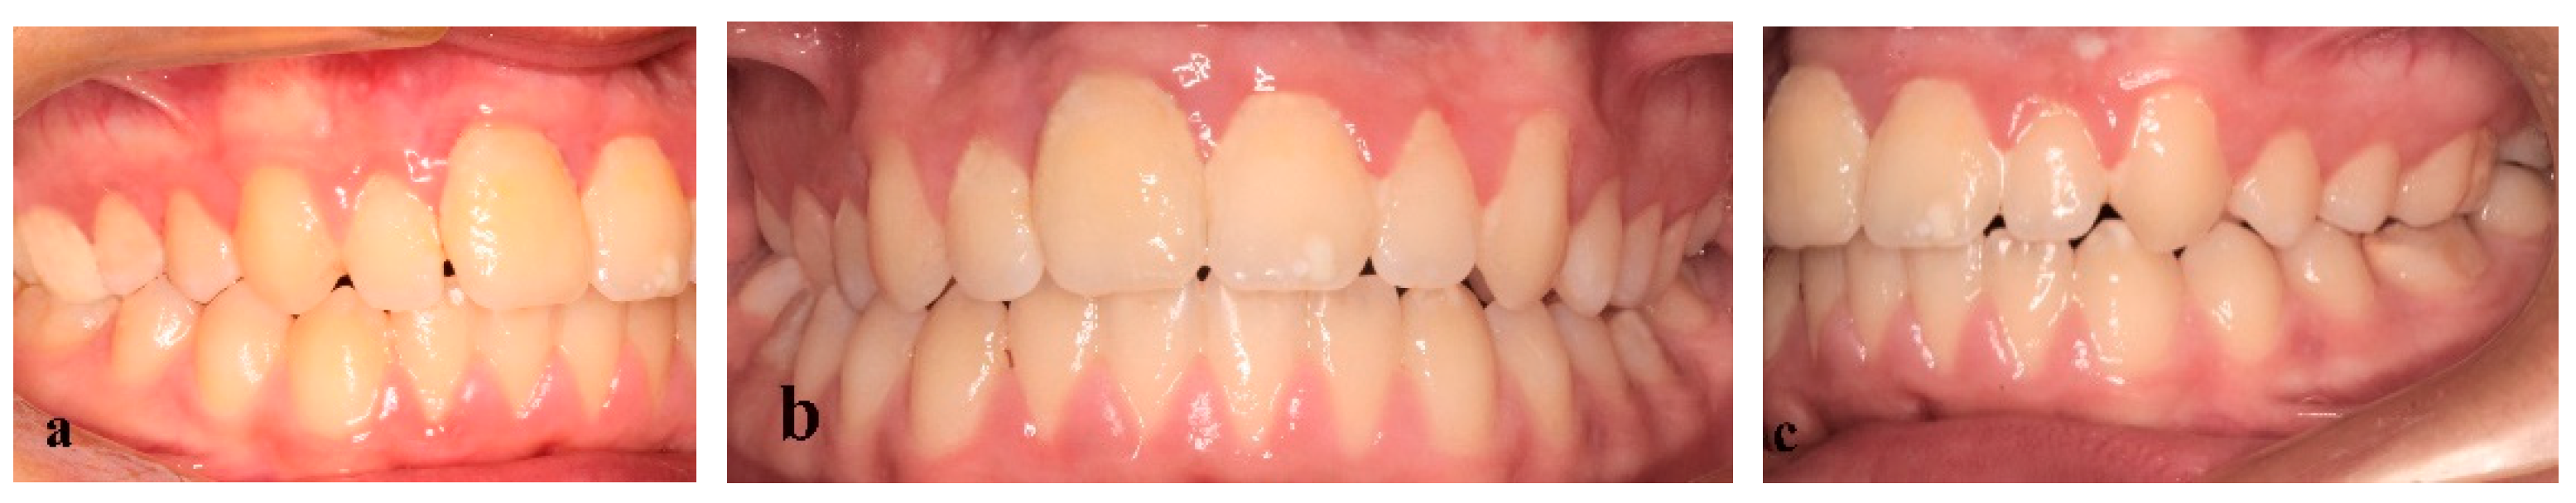

3. Results